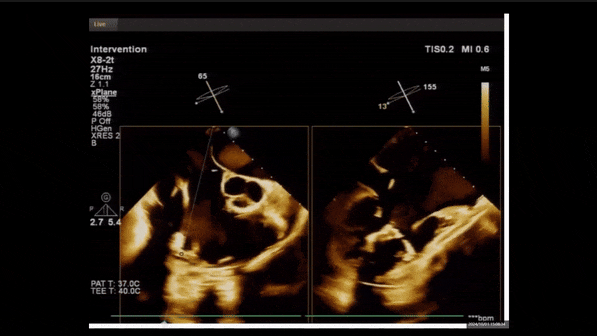

術(shù)前TEE評(píng)估

1、3D TEE顯示雙房及右室擴(kuò)大,右室中段直徑40mm,右室FCA 52%。三尖瓣環(huán)TAPSE 22mm,三尖瓣環(huán)左右徑49mm,三尖瓣隔葉長(zhǎng)度16mm,前葉長(zhǎng)度21mm,后葉長(zhǎng)度34mm,三尖瓣前隔gap 11mm,后隔gap 5.6mm,AP gap 12mm,診斷極重度功能性三尖瓣返流(Type I型三尖瓣:Torrential FTR 5+)。

2、彩色多普勒顯示:收縮期三尖瓣口返流束起源于后隔交界、前后葉之間及前隔交界,返流束縮流頸最大寬度27mm,三尖瓣返流口EOA=2.02cm2,返流容積124ml,收縮期三尖瓣返流峰值速度2.64m/s,返流峰值壓差28mmHg,PAPs 43mmHg,舒張期三尖瓣口平均跨瓣壓差1mmHg,肝左靜脈可見(jiàn)明顯逆向血流波。

術(shù)中經(jīng)食道超聲輔助下可見(jiàn)LuX-Valve Plus夾持件抓捕瓣葉狀態(tài)良好,夾持件在位,室間隔錨定位置良好,假體瓣膜整體錨定狀態(tài)穩(wěn)固。